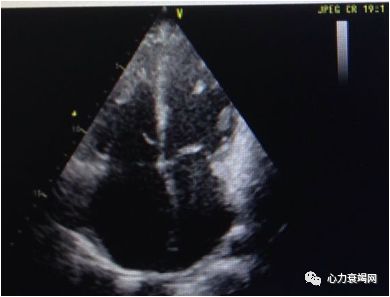

先证者,男,35岁,其父因HCM去世;以心衰入院;

超声显示:EF 25%,室间隔7.3mm,全心增大,左室舒张末径62mm;

先证者在心脏移植术后11天后去世,有一个3岁的儿子。